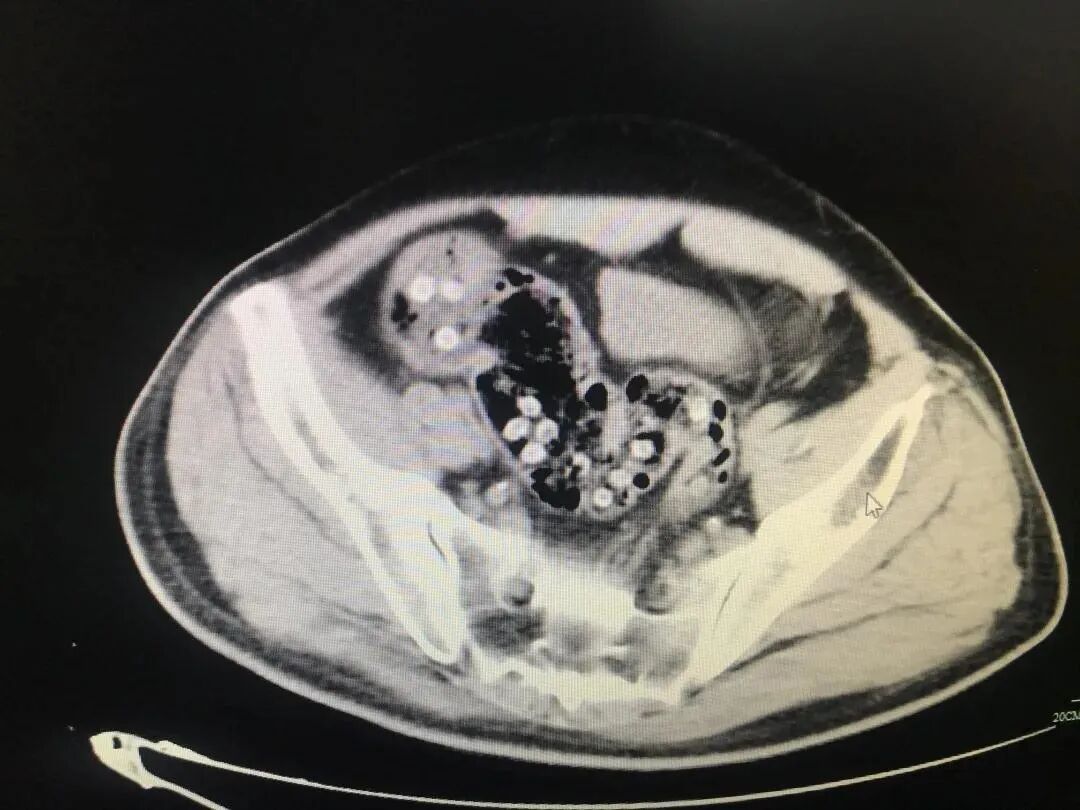

“病人来的时候腹部膨隆明显,上腹疼痛明显,了解到吃杨梅的情况,考虑是杨梅核引起的急性肠梗阻。”急诊科接诊医师解释道。

▲ 白色圆点状的,就是未被排出的杨梅核

医生表示:“年轻人肠道蠕动功能好,即便吞了几颗杨梅核,有些也能自行排出,但随着年纪增长,肠道蠕动功能开始变差、肠壁变薄,吞了杨梅核就容易引起便秘。”